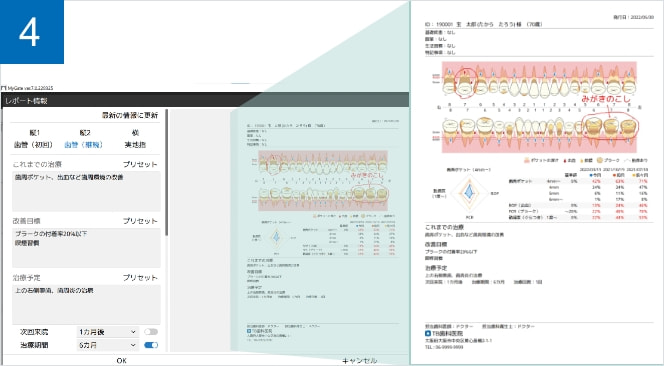

レポート作成機能

患者さんへの説明資料や、保険診療の提供文書の作成ができます。

患者情報や撮影情報、医院情報またメッセージの配置も可能です。

メッセージはあらかじめ登録したプリセットから入力することもできます。

MyGate オプション機能「 X perio(クロスペリオ) 」

歯周病検査の記録やプレゼンテーションを行う事ができる追加可能なオプション機能です。提供文書の印刷までのフローを、スムーズかつ効果的に行えます。

患者説明

検査結果をわかりやすいイラストで表示。

今回・前回・前々回の統計情報とレーダーチャートで経過を確認でき、患者さんのモチベーションの向上・維持に役立ちます。タッチペンで自由に説明を描き込むことができ、説明した内容をそのままMyGateで保存/閲覧することができます。